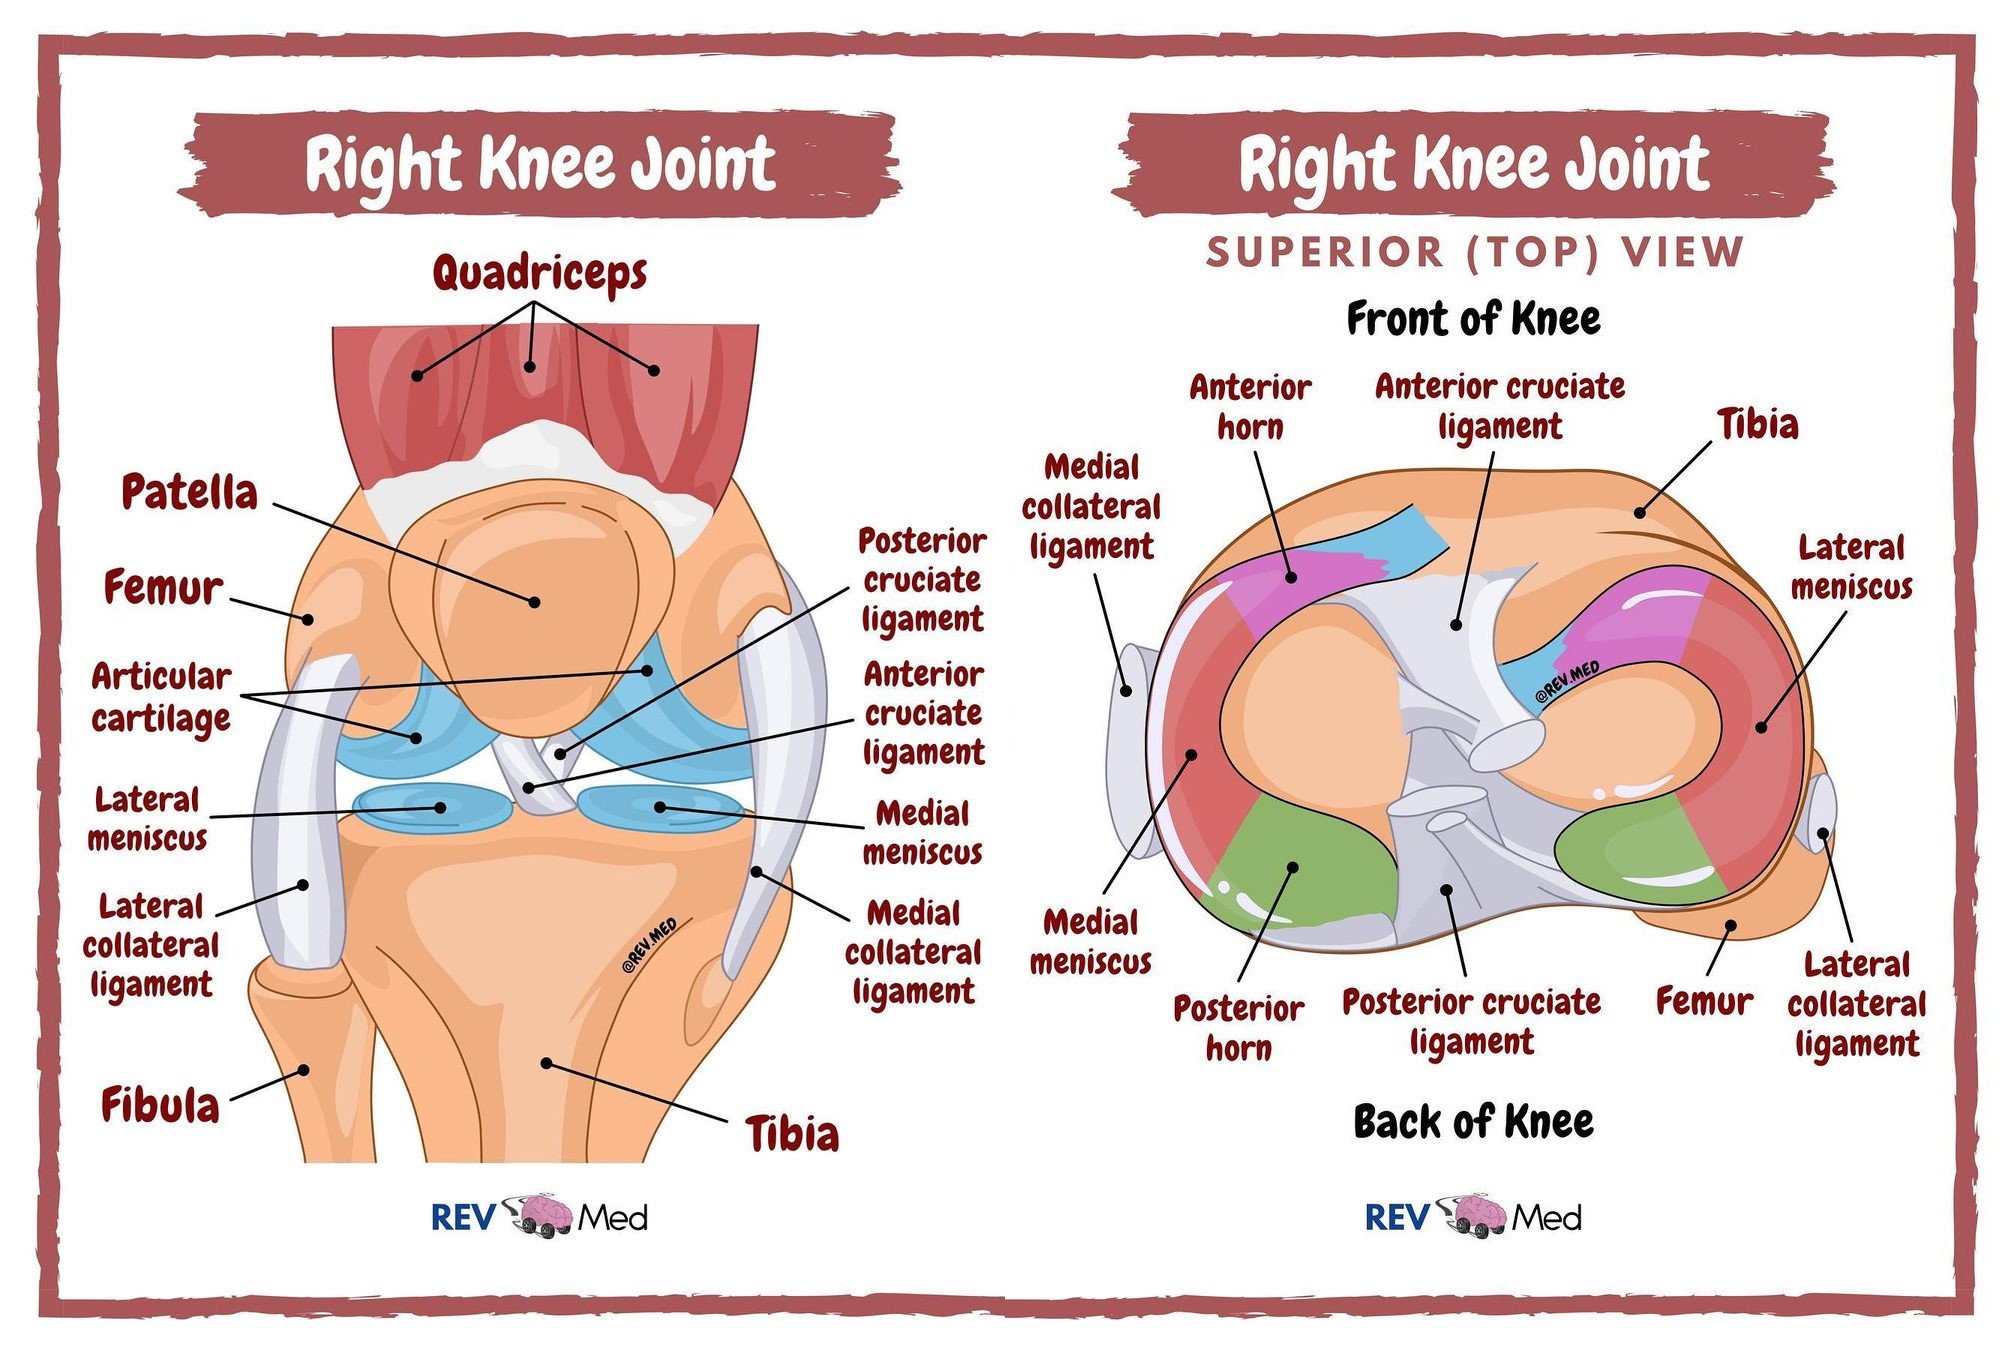

Анатомия и функция на менискусите

Менискусите са структури с полулунна форма, незаменими за правилната биомеханика на колянната става.

Разлики между вътрешния и външния менискус

Вътрешен менискус

Външен менискус

Кръвоснабдяване и възможност за възстановяване

И двата менискуса имат:

добро кръвоснабдяване във външната си зона (до капсулата);

липса на съдове във вътрешния ръб.

👉 Това означава, че:

разкъсванията във външната зона имат потенциал за заздравяване;

вътрешните разкъсвания не се възстановяват спонтанно, поради което често изискват хирургично решение.

Схематично изображение на колянна става с нейните връзки и менискуси